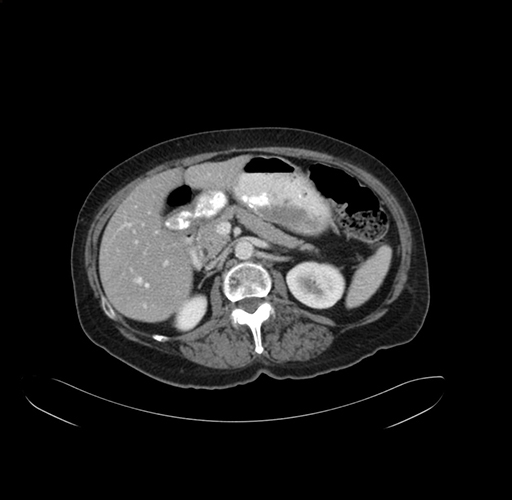

Pre-Chemo: Axial Venous

Axial Venous